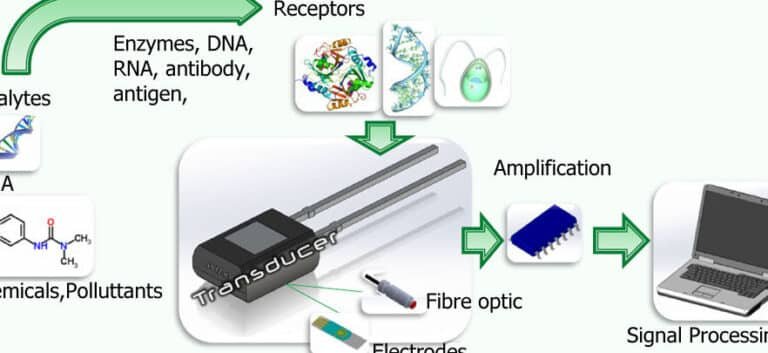

promete revolucionar la medicina al ofrecer un monitoreo preciso y mínimamente invasivo de la salud. Estos dispositivos,...